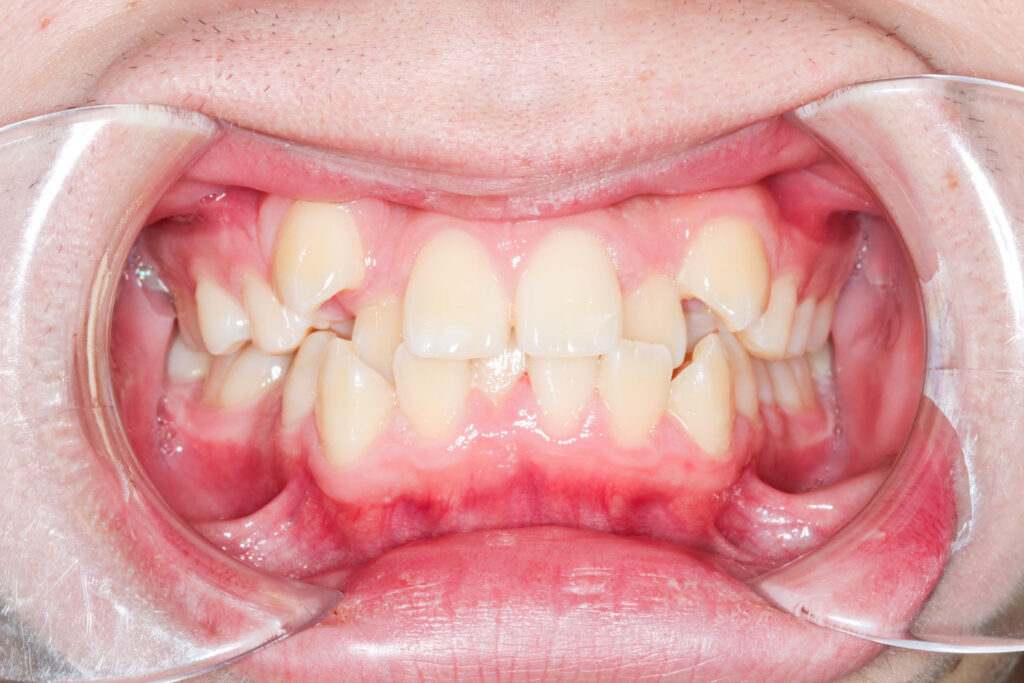

Before

年齢 10代

治療装置 上は裏側の矯正装置(フルリンガル)

治療内容 非抜歯

治療期間 2年8か月

リスク 歯の移動に伴う痛み、歯肉退縮、歯根吸収、歯肉炎、虫歯

主訴 ガタガタと隙間が気になる

症状 叢生と正中離開

治療回数 36回程度

総額費用 140万円程度